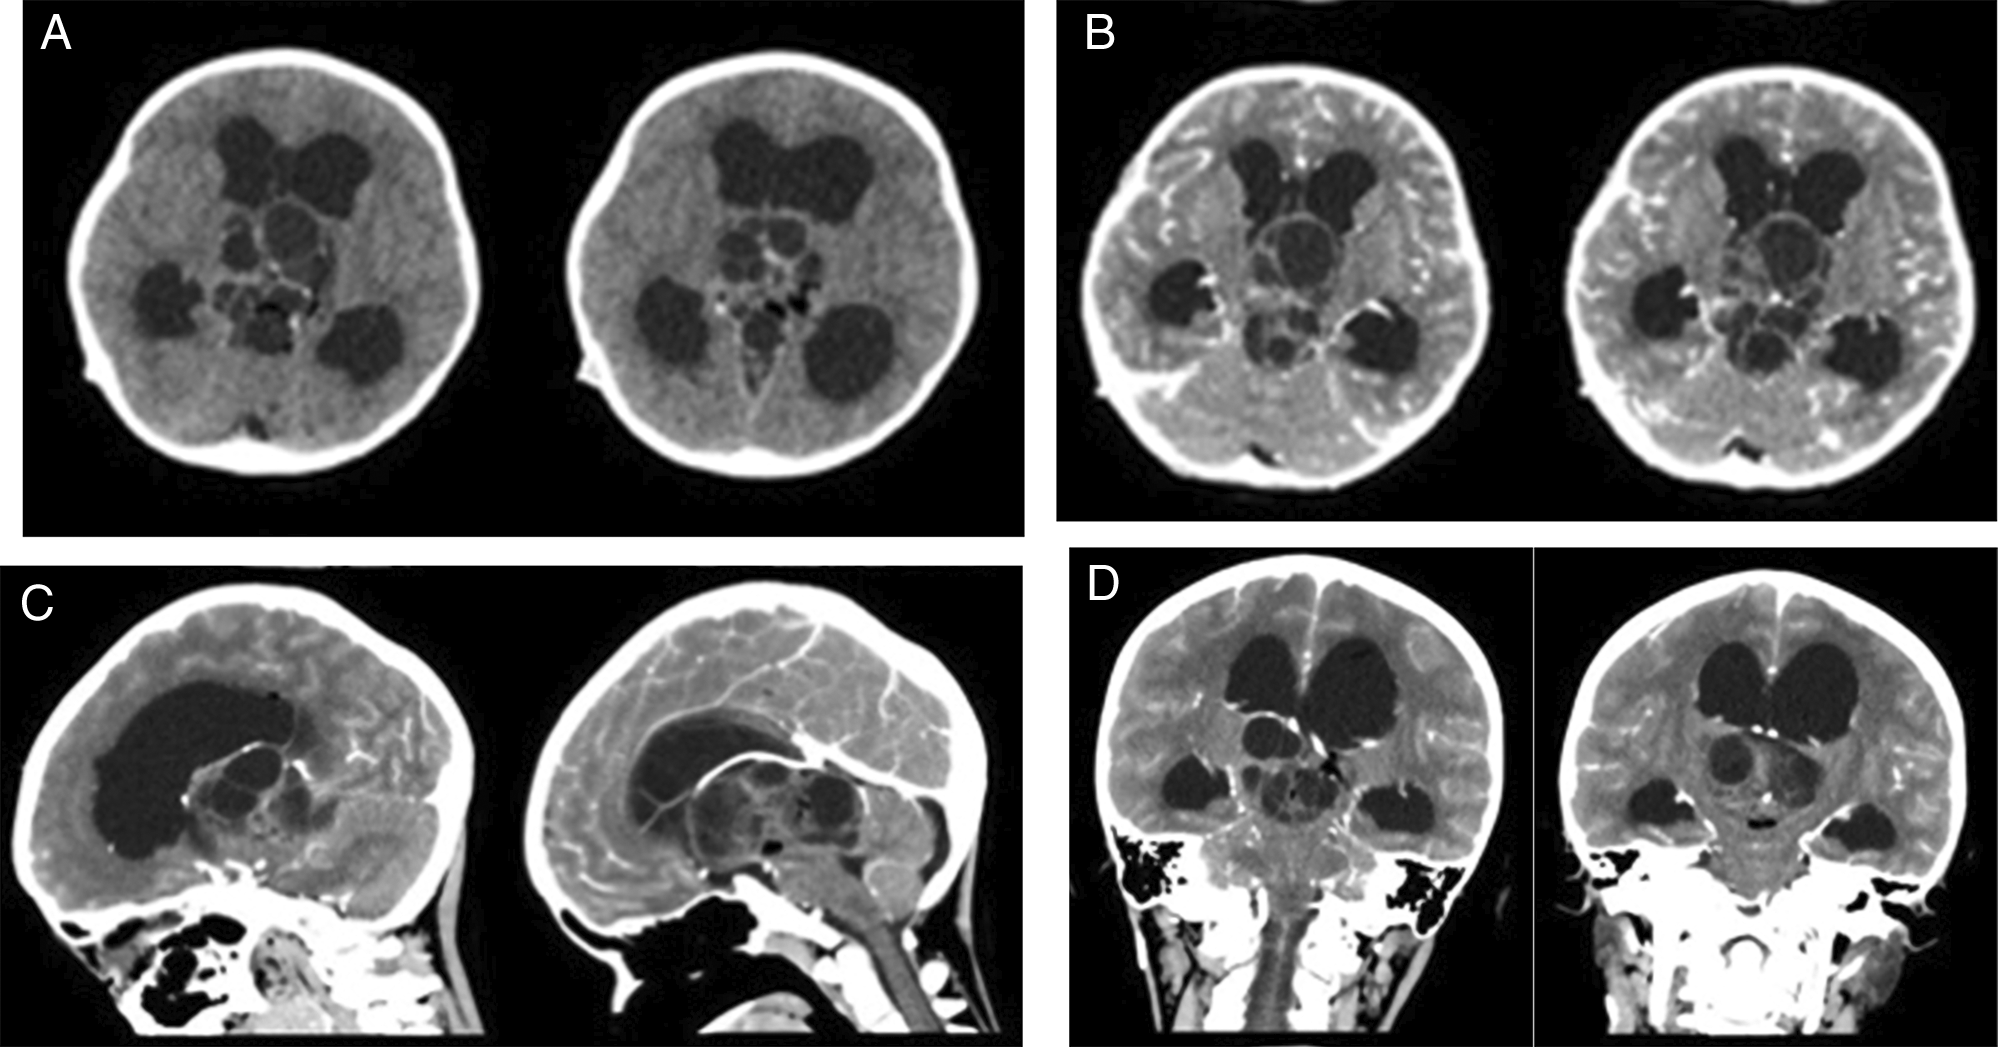

An 8-year-old boy presented to our center with a history of decreased consciousness, generalized seizures, progressive headache, and vomiting one week prior to admission to our hospital. The patient had previously undergone a VP shunt for communicating hydrocephalus because of tuberculous meningitis 1 year prior and clinically improved. He underwent a head CT scan due to this latest clinical deterioration, which showed hydrocephalus with a lobulated cystic and solid mass in the 3rd ventricle. Subsequent contrast-enhanced CT imaging indicated the presence of vascular structures surrounding the tumor. The internal cerebral vein was visible, crossing beneath the tumor (Figure 1). The patient also underwent contrast head MRI, and the result showed a well-defined multiloculated mass with cystic and solid components filling the 3rd Ventricle which was enhanced inhomogenously with gadolinium contrast administration and enlarged lateral ventricles (Figure 2). An endoscopic tumor biopsy was performed, and the histopathological results suggested that the tumor was an arachnoid cyst.

In terms of imaging modalities, intracranial teratomas often present as single or multiloculated ovoid or lobulated masses. Intracranial teratomas are frequently observed to have fatty components, cystic areas, and calcifications on CT images.13 In MRI, teratomas usually appear as well-defined masses with mixed signals on T1- and T2-weighted images. Fatty and highly proteinaceous material typically appear brighter on T1WI, while calcification and blood are usually darker on both T1WI and T2WI. The cystic, solid, and hemorrhagic regions showed varied signals on T2WI. Gadolinium contrast enhancement is generally heterogeneous.2 Liu et al. (2013) showed that malignant teratomas exhibit significant irregular enhancement on contrast-enhanced T1-weighted images, indicating vascular proliferation in the solid region of the tumor. This marked enhancement is key to differentiating between mature and malignant teratomas.10